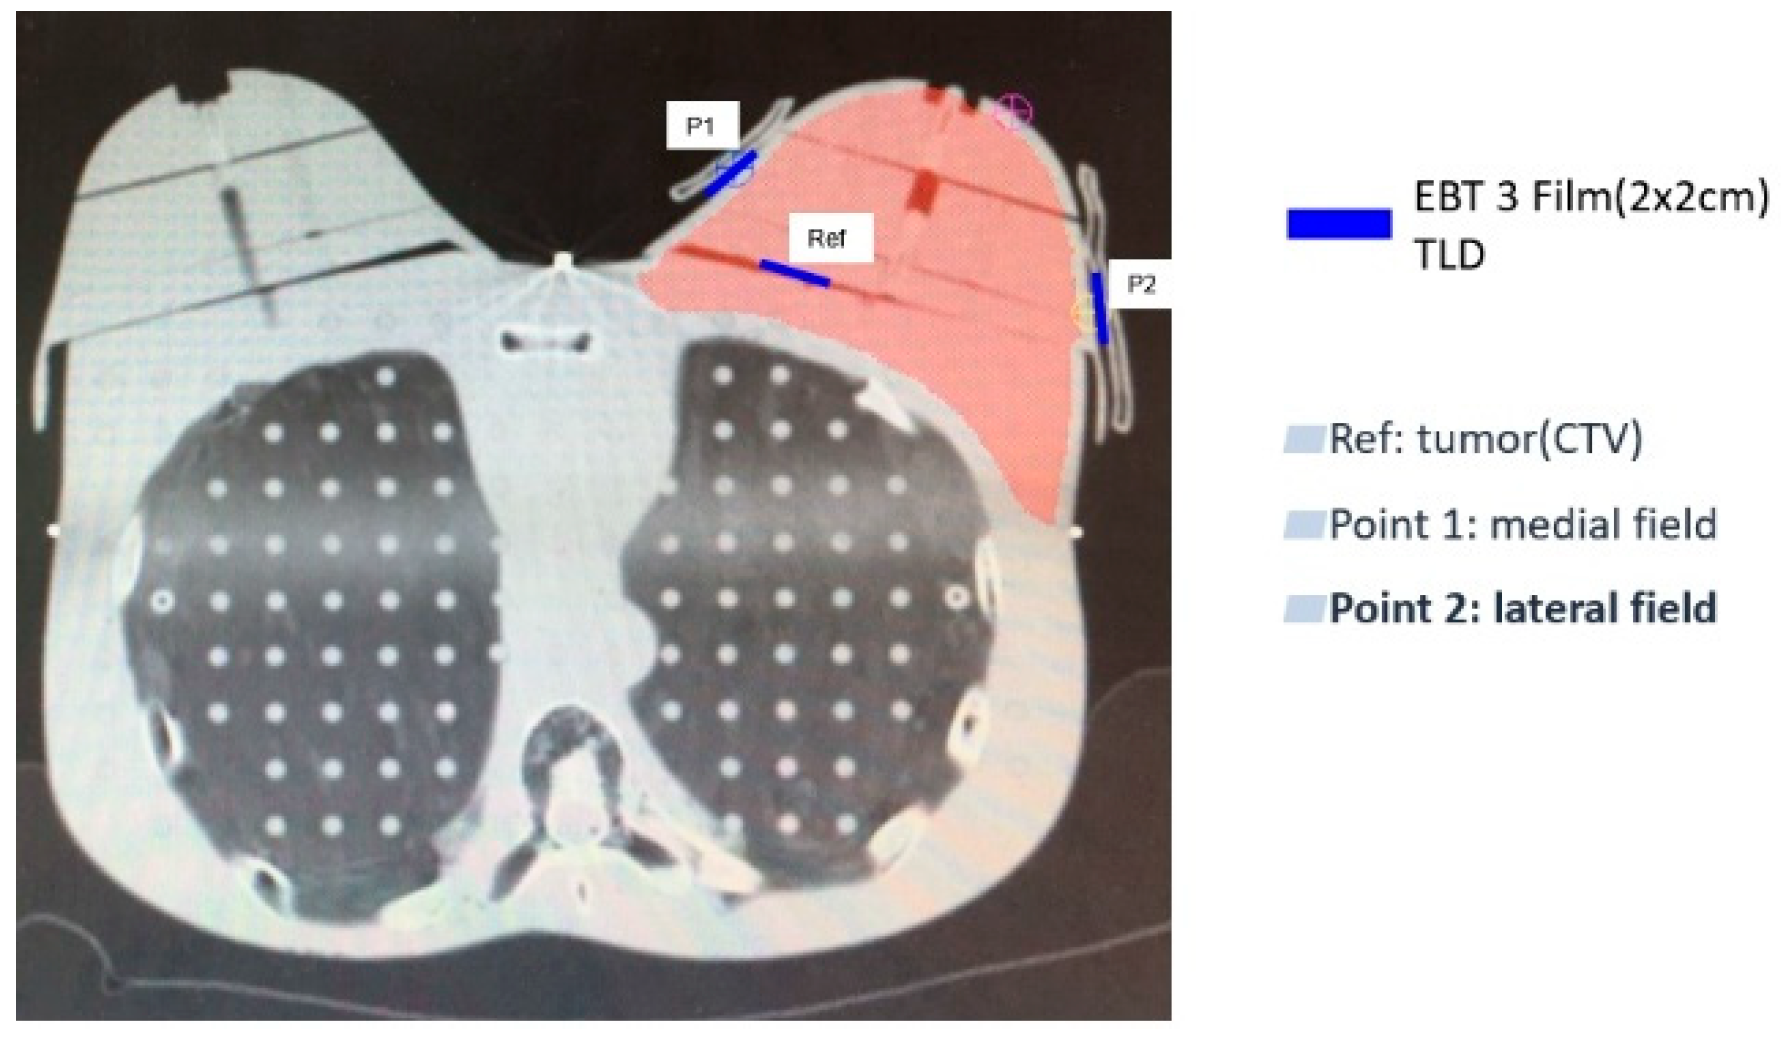

2.3. Surface Dose Measurement

2.3.2. Patient